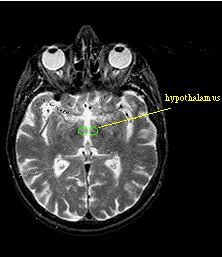

Limbic System and Hypothalamus

Limbic system

- Regulates internal environment of the body

- Autonomic nervous system

- Hormones

- Drive states